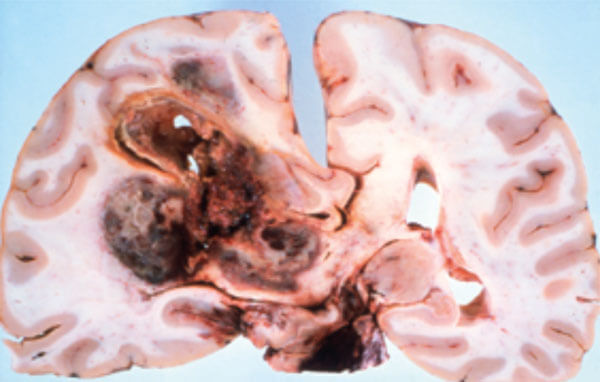

Figure 5: Pathology of an infiltrating glioblastoma with extensive haemorrhage.

Astrocytomas comprise up to 50% of primary brain tumours and can originate anywhere in the brain parenchyma, often presenting with seizures; the more benign varieties are commonest in the fourth decade of life but the GBM is usually seen in the fifth or sixth decade (Figures 4 and 5).